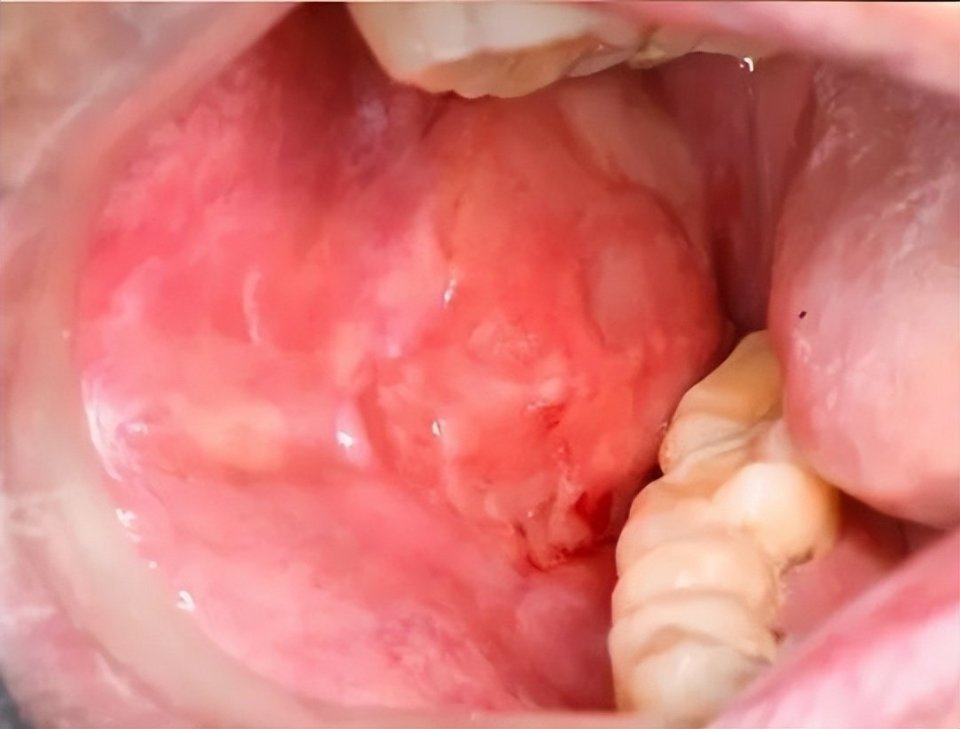

溃疡形成及苔藓样损害(图片源自陶人川教授团队)

诊断性口腔表征:移植后口腔黏膜出现苔藓样改变,表现为角化过度的白色条纹或网状病变,可伴或不伴红斑、溃疡。一旦出现此典型表现,即高度提示口腔cGVHD。

溃疡多继发于或合并苔藓样损害背景,常伴上述典型口腔表征。值得警惕的是,口腔cGVHD属于口腔潜在恶性疾患,对于长期不愈、质地改变的溃疡病损建议及时活检明确病损性质。